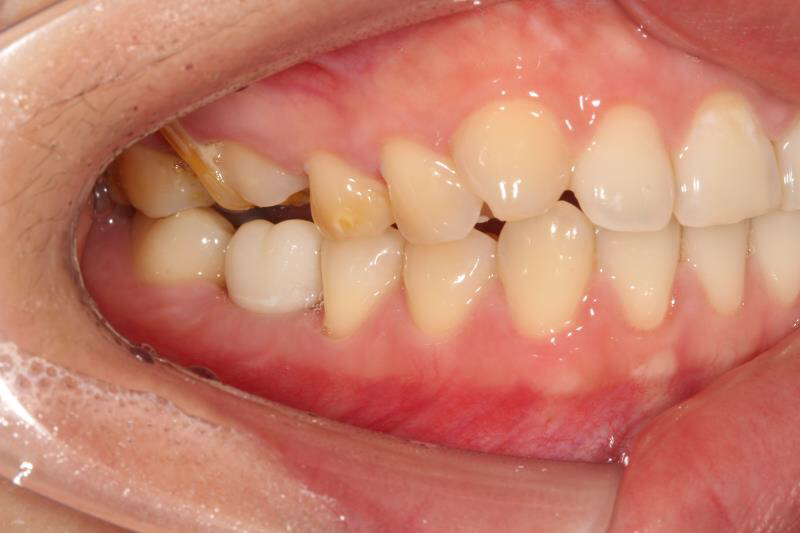

今天给大家介绍一个单颗后牙种植+局部正畸联合治疗病例。

患者年轻女性,后下6残根,因未及时修复,5、7号牙向6号牙倾斜,导致了修复空间不足。按照常规治疗方案,会损伤两侧的健康牙齿,得不偿失,所以我们为她采用了正畸+种植联合治疗方案。